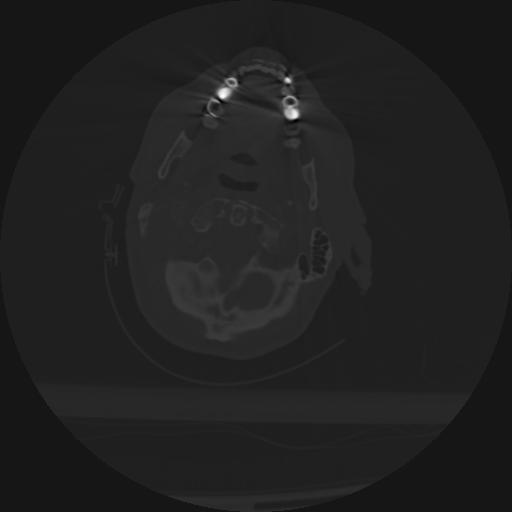

22 ANGIO,CE,Vol,0.5,ANGIO,,